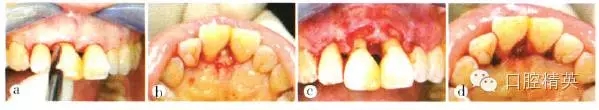

患者全身狀況良好,無過敏史及長期服用藥物史,否認(rèn)吸煙史??谇粰z查:口腔衛(wèi)生尚好,菌斑、軟垢少,牙石+~++;個別牙齦輕度紅腫,出血指數(shù)(bleeding index,BI)為1~3,654 456牙齦退縮明顯;全口探診深度(probe depth,PD)3~5 mm,附著喪失,根分叉病變(furcation involvement,F(xiàn)I)個別1~2度,無松動;7缺失,1先天缺失,雙側(cè)第一磨牙近中關(guān)系。高位笑線,前牙I度深覆蓋,211牙冠呈尖圓形,牙齦退縮約1.3 mm,齦乳頭缺失,屬M(fèi)iller III類.鄰面根頸部可見“黑三角”(圖1)。

a上前牙區(qū)正面觀;b上前牙區(qū)牙合面觀;c上前牙區(qū)腭側(cè)觀;d患者微笑像,可見上前牙區(qū)存在“黑三角”;e上前牙區(qū)側(cè)面觀

圖1初診時上前牙區(qū)口內(nèi)像及微笑像